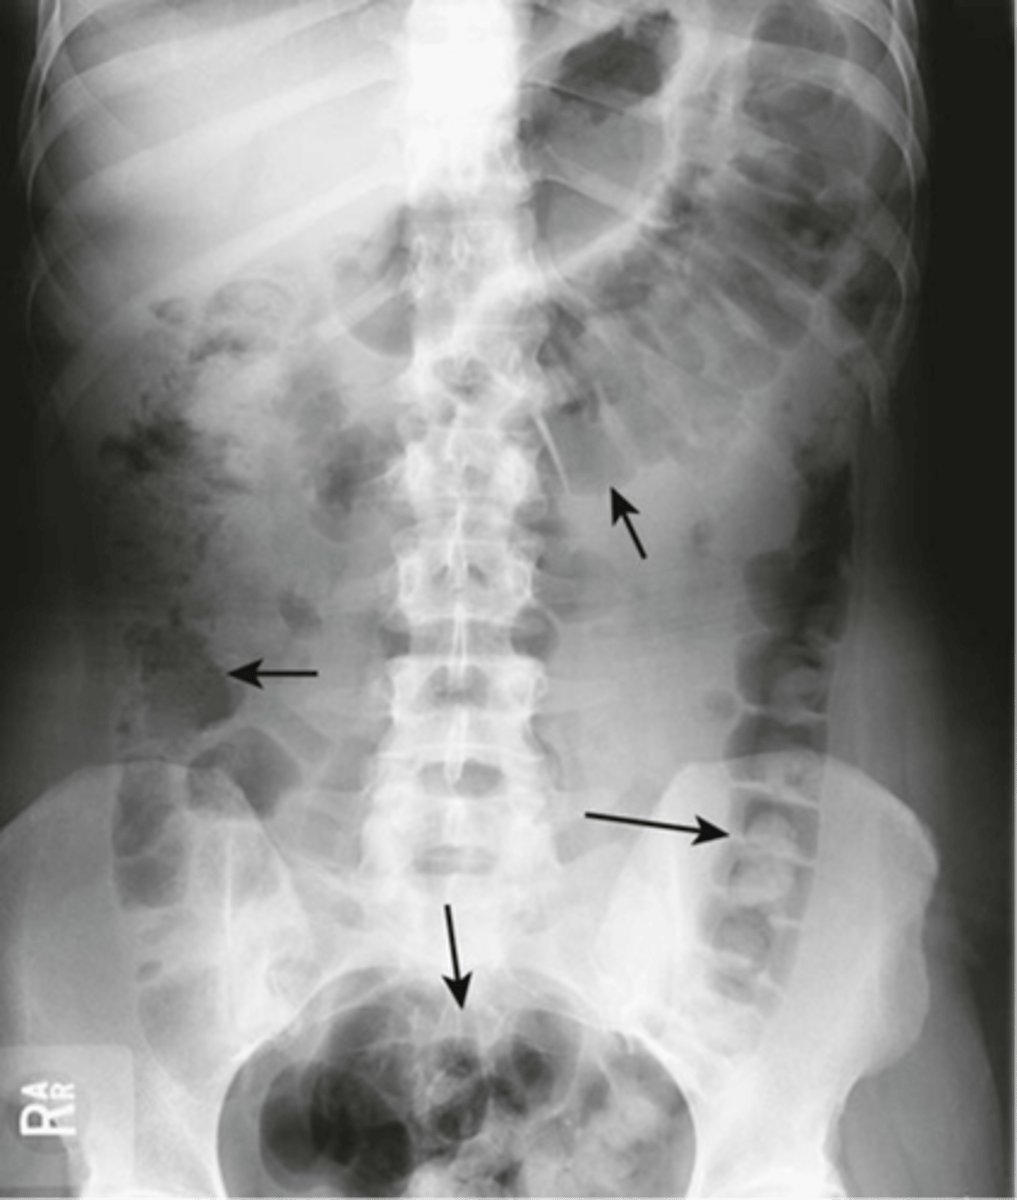

Normal bowel gas pattern

Normal supine AXR

Normal AXR (and normal size liver)

Normal AXR (and normal organs)

Normal AXR (and normal structures)

Large bowel Haustra

Large bowel haustra (pic 2)